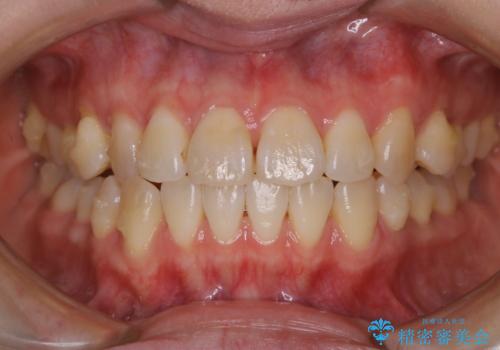

- 前歯のがたつきが気になるとご相談にいらした方です。右側前歯部のクロスバイトの他、左側にもシザーズバイトが認められたため、インビザラインにて治療を行いました。出産直後のため、ご自身の時間がなかなか取れないとの事で、最小限の来院回数で治療を勧められるように計画しました。

患者様ご自身で使用時間をしっかり管理して頂くことを条件に、最低限の来院回数で治療を進めていきました。20時間以上の使用を厳守して頂けたことで、少ない来院回数にて治療を終了することが出来ました。前よりも噛みやすくなったと大変喜んでいただけました。